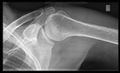

أشعة إكس